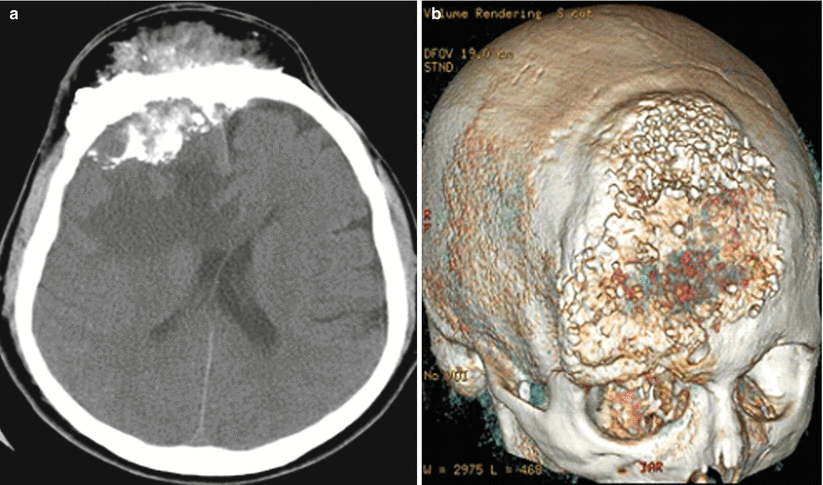

Последствие менингиома

Последствие менингиома 114 фотографий